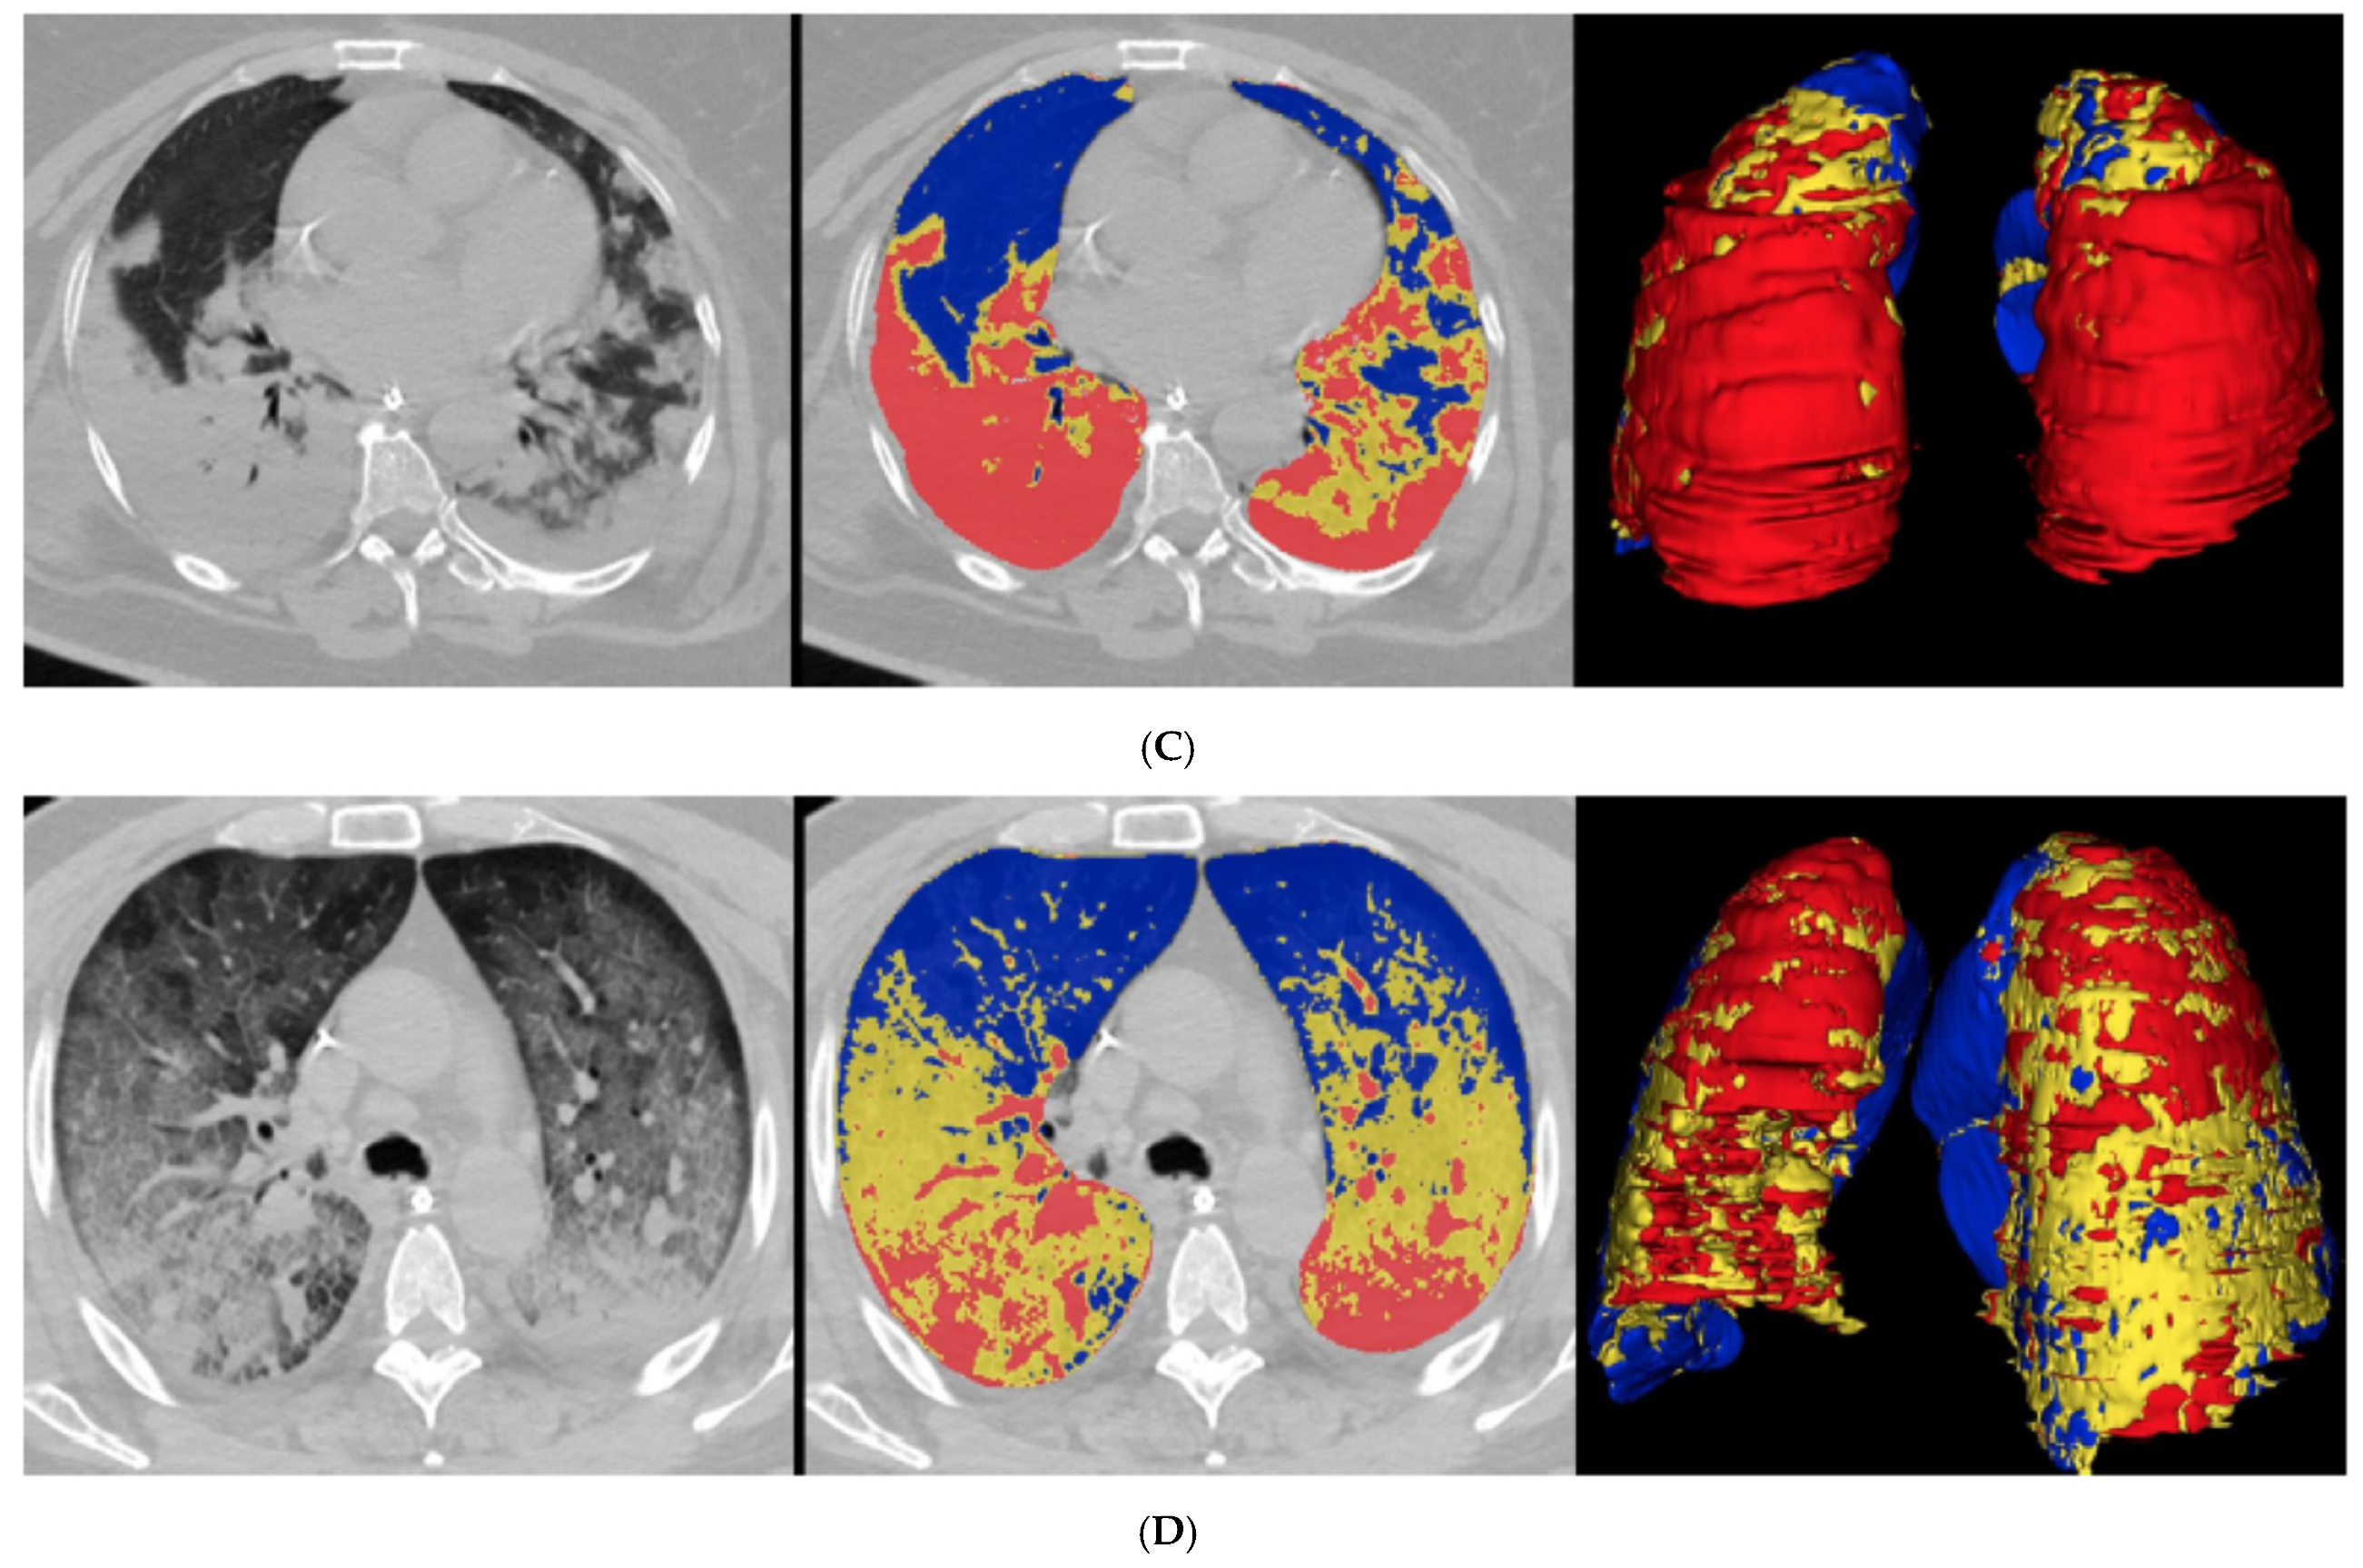

All CT scans were of satisfactory quality for analysis. Case examples of QCT with %CL < or >23% and different texture between %PAL and %NNL are illustrated in Figure 1. Median %CL was 16% in the deceased group (IQR, 10–32%) and 11% in the recovered group (IQR, 6–19%). The difference proved statistically significant (p < 0.001; Table 2).

Figure 1.

Unenhanced CT scan and QCT analysis in four patients with COVID-19 pneumonia. (A,B) show one QCT with %CL < 23% and one with %CL > 23%. (C,D) highlight the texture differences between the “poorly aerated” volume (%PAL, −500, −100 HU) and “non-aerated” volume (%NNL, 100, -100 HU). (A) refers to a 71-year-old man, oxygenated through nasal cannulae. Upon admission, laboratory tests were as follows: D-dimer 199 ng/mL, fibrinogen 416 mg/dL, PT ratio 1.03, CRP 1.0 mg/dL. %CL was 10%. Non-contrast axial chest CT showed ground-glass opacities, predominantly in the middle lobe; quantitative analysis highlights poorly aerated lung volumes in yellow (8% PAL) and normally aerated lung volumes in blue. (B) refers to a 64-year-old man who required mechanical ventilation and intubation. Upon admission, laboratory tests were as follows: D-dimer 1161 ng/mL, fibrinogen 1021 mg/dL, PT ratio 1.18, CRP 45.3 mg/dL. %CL was 55%. Non-contrast axial chest CT showed diffuse bilateral ground-glass opacities and posterior lung consolidation; quantitative analysis highlights non-aerated lung volumes in red (19% NNL), poorly aerated lung volumes in yellow (36% PAL), and normally aerated lung volumes in blue. (C) refers to a 65-year-old woman who required mechanical ventilation and intubation. Upon admission, laboratory tests were as follows: PT ratio 1.34, CRP 31.9 mg/dL. %CL was 66%. Non-contrast axial chest CT showed extensive posterior consolidation of the right lower lung lobe and patchy dense consolidation in the subpleural space of both left lower and upper lung lobes; quantitative analysis highlights poorly aerated lung volumes in yellow (23% PAL) and non-aerated lung volumes in red (43% NNL). (D) refers to a 66-year-old man who required mechanical ventilation and intubation. Upon admission, laboratory tests were as follows: D-dimer 1335 ng/mL, fibrinogen 832 mg/dL, PT ratio 1.20, CRP 33.8 mg/dL. %CL was 62%. Non-contrast axial chest CT showed extensive ground-glass consolidation with “crazy paving” pattern typical of COVID-19; quantitative analysis highlights normally aerated lung volumes in blue, non-aerated lung volumes in red (12% NNL), and poorly aerated lung volumes in yellow (50% PAL).